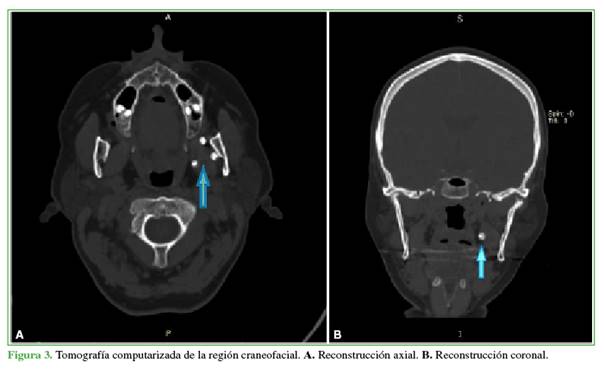

Para precisar la ubicación exacta de las lesiones y llegar a un diagnóstico se decidió solicitar una tomografía computarizada de la región craneofacial con reconstrucción en 3D. En las imágenes, se apreciaron las calcificaciones nodulares en posición medial respecto a la rama mandibular izquierda, en relación con el músculo pterigoideo medial (Figuras 3 y 4).